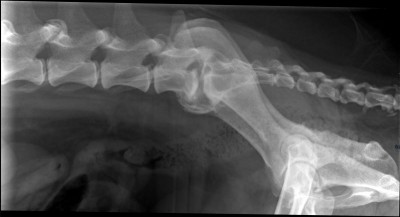

Na pierwszy rzut oka widać, że psiak ma znaczne problemy z poruszaniem się. Bamberek porusza się sztywno i stwierdzono u niego kulawiznę II stopnia na prawej tylnej łapce. Ma również widocznie osłabiony odruch korektury, zwiększone napięcie mięśni lędźwiowo-biodrowych, ograniczenie w odwodzeniu stawów biodrowych oraz obniżenie napięcia mięśniowego mięśni udowych. Na zdjęciach RTG widać u niego dysplazję stawów biodrowych, zmiany zwyrodnieniowe i stany zapalne, które z pewnością sprawiają mu ból :(

Niestety to nie koniec jego ortopedycznych problemów. W badaniu fizykalnym Pan doktor stwierdził zwiększoną bolesność odcinka lędźwiowo-szyjnego kręgosłupa. Na RTG kręgosłupa ma widoczne zmiany typowe dla zaawansowanej postaci zespołu końskiego ogona, zaawansowaną spondylazę a na domiar złego przewężenia w przestrzeniach międzykręgowych m.in. w odcinku szyjnym co ma wpływ na jego czucie (kwestie neurologiczne) i stanowi ryzyko paraliżu w przyszłości :(

Miednica 2.jpg

Miednica 1.jpg